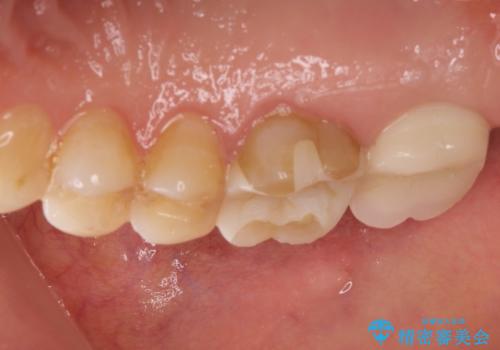

感染した奥歯 痛くて咬めない 根管治療→かぶせ物で痛みを取り除き、かみ合わせを回復する

- 古い詰め物を除去し、腐ってしまった神経を顕微鏡下で丁寧に処理する

→根管治療完了後、土台を築造し、かぶせ物を製作してかみ合わせを回復する

すでに感染が根の先端まで及んでいたため、かなり強い痛みがありましたが、丁寧に根管治療をすることで内部を可及的に無菌化し、痛みが消失しました。